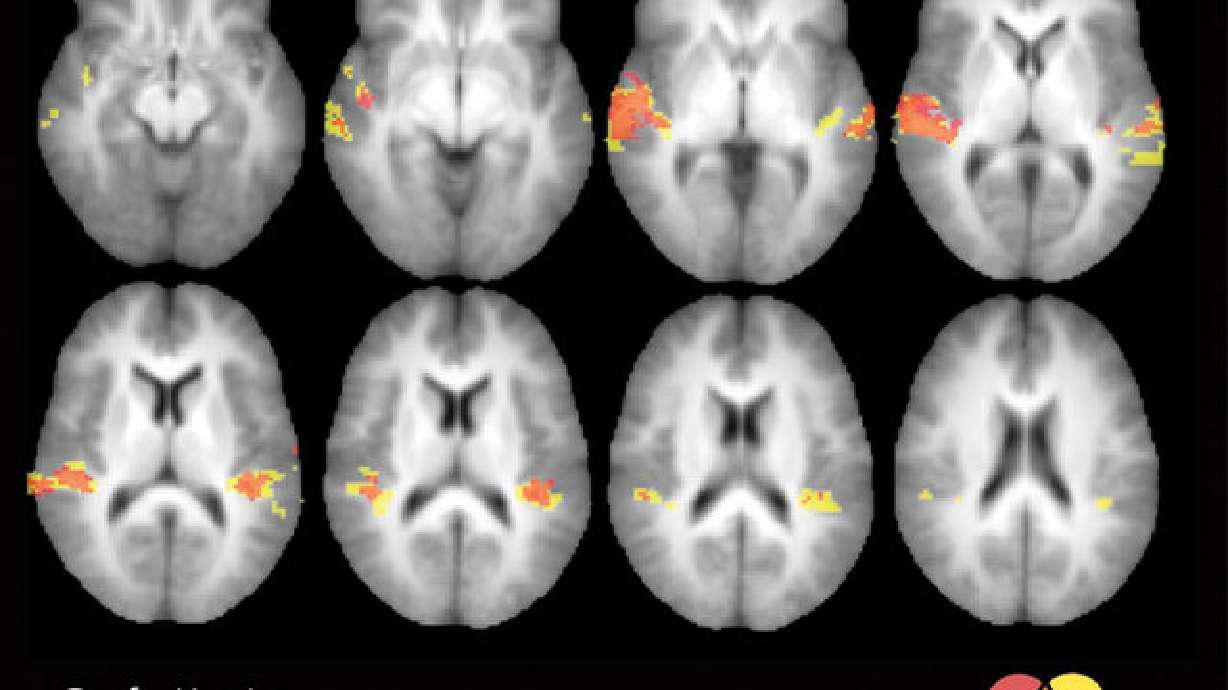

The study used a headphone-like device with flexible tubing that puffed air above the right eyebrow and on the right cheek. At the same time the tubes puffed air, fiber optic cables attached to the headgear would emit a pulse of light. Functional MRI displayed the reaction to both the somatosensory (touch) and visual stimuli in Heschl's gyrus, the auditory cortex and temporal lobe.

Just as hearing people did not all have the same illusion with the sound stimuli, deaf participants in Karns' study with a stronger response in their Heschl's gyrus had a stronger reaction to the illusion.